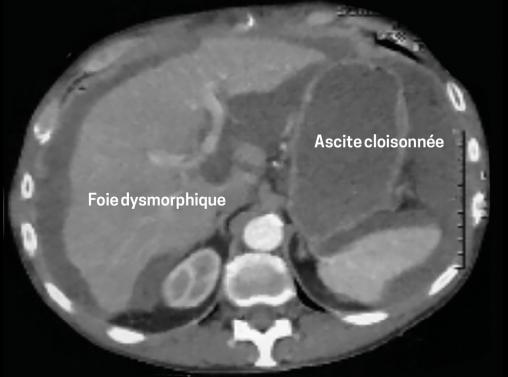

Le scanner abdominal (fig. 1 et 2)montre un volumineux épanchement ascitique diffus, un foie dysmorphique. Le bilan d’hépatopathie est négatif. L’ACE est élevé (8,79 µg/L), comme le CA 19,9 (57 UI/mL).

La tomodensitométrie et l’échographie apportent des signes radiologiques complémentaires : respectivement encoches hépatiques et images de cloisons.